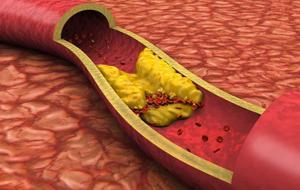

Tüm dünyayı kasıp kavuran Covid-19 virüsünün insanlar üzerinde birçok etkisi bulunuyor. Kardiyoloji Uzmanı Doktor İsmail Erdoğu, Covid-19 virüsünü geçirmiş olan hastaların kalp kasında iltihaplanma görüldüğünü belirterek, “2019 yılından beri bir endemik salgın yaşıyoruz. Tüm dünya üzerinde etkisi olan bir salgın, hala daha geçmiş değil. Aşılarımızı olduk ama ne yazık ki hastalıktan kurtulamıyoruz. Hastalık özellikle akciğerler olmak üzere vücudun bütün organları etkiliyor. Dünyadaki en yaygın hastalıkların kalp hastalıkları olduğunu düşünüyoruz. Buna bağlı olarak bu virüsün özellikle kalp hastalıklarında etkili hale geldiği görülüyor. Virüsü geçiren hastalarımızda özellikle virüse bağlı olarak kalpte kalp kasında iltihaplar gözleniyor. Aynıca kalp krizini tetiklediğini görüyoruz. Virüsün direk kalp kasına etkisi çok yaygın değil. Sıklık olarak binde 1 ile 3 civarında görülüyor” dedi.

Kalp krizi daha ölümcül

Doktor Erdoğu, kalp krizi nedeniyle ölüm oranlarının Covid-19'a göre yüksek olduğunu söyleyerek, “Covid-19'a yakalanıp ölme sıklığıyla kalp krizine yakalanıp ölme sıklığı kalp krizinde çok daha yüksek. Dolayısıyla bizim gibi toplumlarda sağlıklı yaşamadığımız için kalp hastası olma ihtimalimiz daha yüksek diğer toplumlara göre. Ama bir yandan da Covid-19'dan korkup hastaneye gitmeyince kalp kriziyle acillere gitmek zorunda kalıyoruz” ifadelerini kullandı.